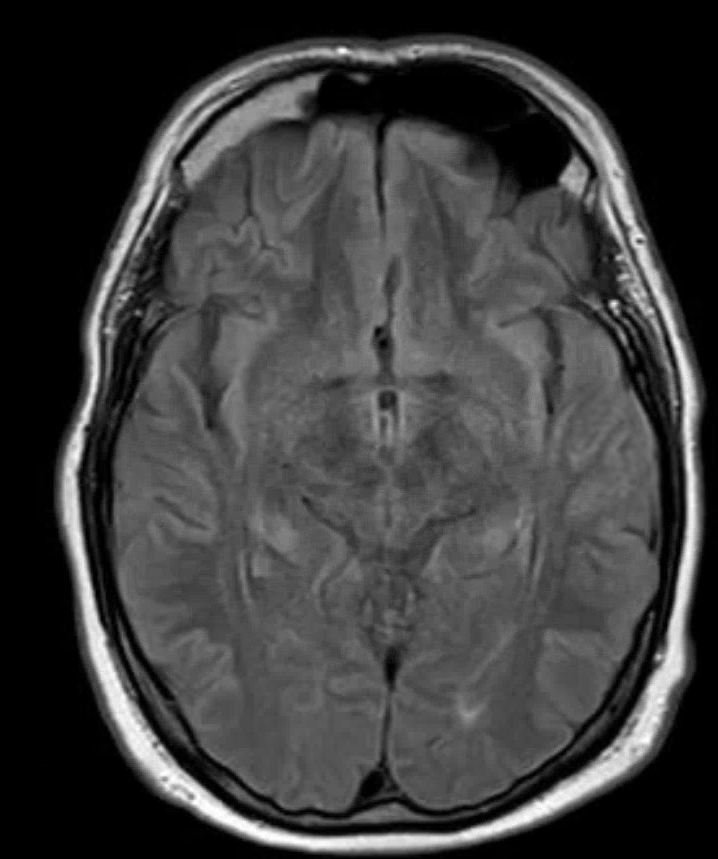

Das MRT hat von allen apparativen Verfahren noch die höchste Sensitivität, eine Wernicke-Enzephalopathie zu entdecken, da es aber insbesondere bei leichteren Fällen zwar histopathologische – aber keine MRT-morphologischen – Veränderungen gibt, schließt ein unauffälliges MRT eine Wernicke-Enzephalopathie nicht aus.